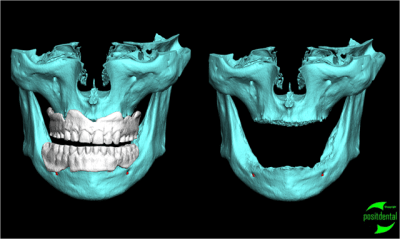

Pour la réalisation d'un all on 6 haut et bas avec MCI durant la même opération , je fabrique un renfort en inox pour la prothèse provisoire. Ainsi on obtient un ensemble transitoire parfaitement rigide.

Je réalise l'ensemble, guide chirurgical de forage, positionneur d'implants et armature du provisoire à partir des images native DICON du scanner. Dans ce cas la chirurgie et la mise en fonction de la prothèse transitoire ont été effectuées en une opération.

Pour réaliser ce travail j'ai eut besoin du montage haut et bas sur cire.

1 je confectionne un guide radiologique.

2 après le scanner le patricien garde les planches et m'indique l'emplacement et le choix des implants et m'envoie le CD du dentascan

3 par e-mail je retourne l'étude avec des coupes, mise en situation et densité osseuse qui permettent d'évaluer la fixation primaire et la stratégie du forage

4 le guide, le provisoire, la reconstitution osseuse en stéréo lithographie, le tout fabriqué au labo puis livré avec un délai suffisamment nécessaire avant l'intervention pour être contrôlé physiquement et le guide inox stérilisé.

la réussite chirurgicale de cette intervention revient au Docteur Jean KOSKIEVIC (Paris).